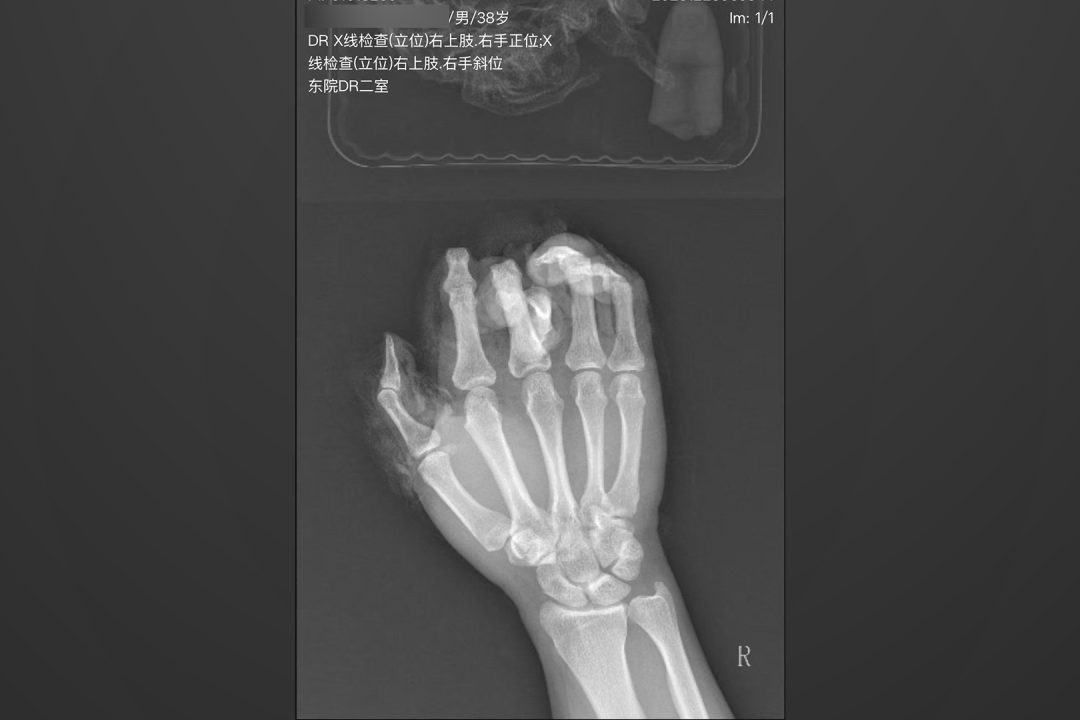

当天早上,吴先生(化名)的右手不慎被机器绞伤,被紧急送到烟台山医院。检查发现,其右手拇指、食指、中指完全离断,且损伤类型极为特殊——并非整齐切断,而是皮肤、软组织像“脱手套”一样,从近端向远端呈现“手套状”撕脱,骨骼、肌腱、血管及神经被暴力抽出,损伤范围巨大,污染严重。

患者的手像被“扒皮抽筋”一样,皮肤软组织从手指上整体撕脱下来。

“这是手外伤中最复杂、最棘手的情况之一,三指同时发生完全性脱套离断,更是罕见。”东院手外伤二科主治医师程旭表示。与断面整齐的普通断指不同,脱套离断伤的血管、神经长段缺损,创面条件极差,再植难度堪称手外伤科领域的“珠穆朗玛峰”。

此类手术面临多重极限挑战:血管条件极差,主干血管内膜严重损伤,需进行血管移植,并需在残存的微小血管网中,寻找并吻合直径仅0.3至0.5毫米、细如发丝的血管;神经重建复杂,常需移植;皮肤覆盖困难,撕脱皮肤多已坏死,需从身体其他部位移植带血运的皮瓣;多指同时手术,耗时漫长,对医生的体力、精力及团队协作能力都是严峻的考验。

手术团队首先进行精细清创,在显微镜下仔细辨别并标记每一处可供吻合的微小血管与神经。随后,将离断的指骨与关节精准复位固定,搭建手指的“骨架”,并缝合肌腱与神经。最核心、最艰难的环节是血管移植与吻合:医生从前臂切取静脉,桥接移植至三根手指的动脉与静脉,并与残留的、直径不足0.5毫米的微小血管进行超显微吻合。血管壁薄如蝉翼,要求操作绝对稳定精准,任何微小失误都可能导致吻合口栓塞,手术前功尽弃。